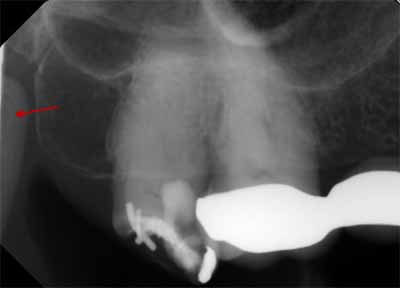

上顎のさらに奥には、臼歯があります。この領域には、X線画像に投影されるさまざまな解剖学的構造がいくつかあります。上顎洞の下部(画像10および画像14を参照)がさらに詳しくわかり、多くの場合、外後頭隆起も確認できます。この構造はエックス線不透過性が高く、「U」または「V」の文字のような形をしています。外後頭突起は主に上軸投影時に画像化され、大臼歯の歯根尖と重なる可能性があり、病変が隠れる危険性があります(画像13を参照)。

頬骨突起の遠位側には頬骨弓の下縁があり、わずかにエックス線不透過性の弓として描かれています (画像13を参照)。